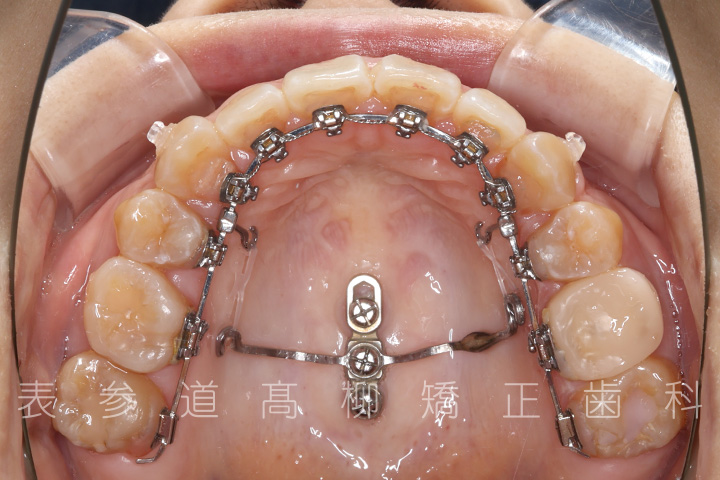

・金属アレルギーのため、マウスピース型矯正装置を多く設定し、ワイヤーでの矯正治療期間を短縮

・マウスピース型矯正装置と歯科矯正用アンカースクリュー(i-station)を併用し、上顎臼歯部を圧下

・歯科矯正用アンカースクリュー(i-station)を併用し、前歯部を後方へ移動する

・歯科矯正用アンカースクリューを併用し、口下顎大臼歯の近心移動(前方への移動)

・リンガルブラケット装置

・歯科矯正用アンカースクリュー